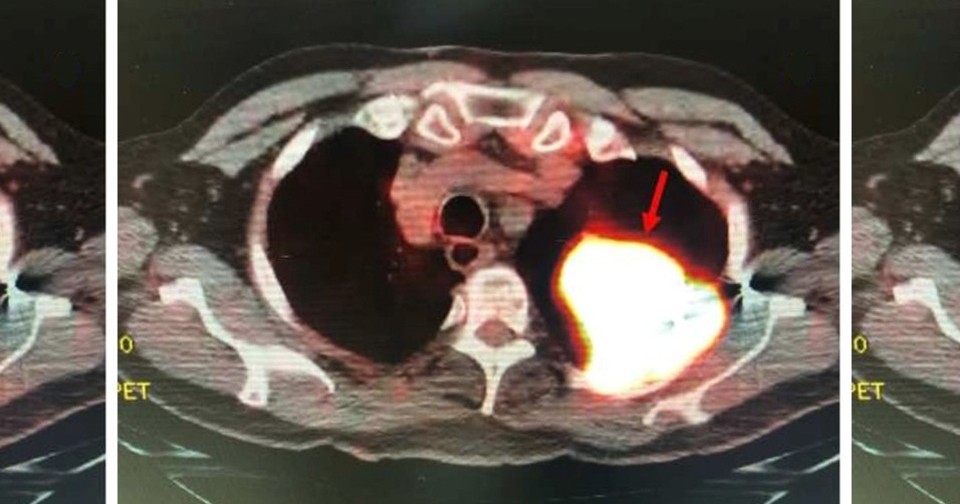

Позитронно-эмиссионная томография выявила изолированное образование в левой верхней доле легкого с локальным поражением грудной стенки без признаков метастазирования. Биопсия легкого подтвердила диагноз мелкоклеточного рака легкого. Врачи удалили пораженную долю легкого вместе с регионарными лимфоузлами.